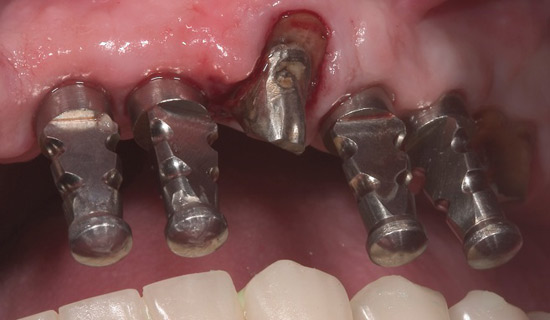

I was lucky – with much support - I commenced a complete dental reconstruction in 2005 - bone grafts, 17 implants and a strong set of gleaming new teeth.